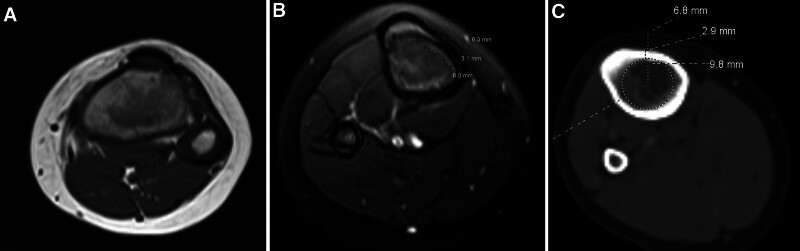

Measurements and main results: A total of 912 scans were initially retrieved; 232 scans were excluded due to osseous diseases, tibial fractures, suboptimal scan quality, or soft-tissue abnormalities, leaving 680 scans for analysis. Scans were stratified into 1-year age groups. Measurements at the proximal tibia included soft-tissue thickness, cortical bone thickness, and medullary canal diameter. Other values, such as the pre-intraosseous space (sum of cortical thickness and soft-tissue depth) and total distance to deep cortex, were calculated. Simulated needle insertions demonstrated that 31.62% of the 15 mm needles were too shallow, failing to reach the medullary canal, whereas 34.85% of the 25 mm needles were too deep, both of which could cause severe complications. A cutoff analysis for needle size based on age rather than weight was also calculated. For the 15 mm needle, 95% CI was not found in any age range, and the highest confidence cutoff was for using the needle in the age range of 0-8 years (91.9%). The 25 mm needle had a 97.8% CI from ages 10-16.

Conclusions: The study reveals significant age-related variability in the proximal tibia's anatomical dimensions, suggesting that standard 15 and 25 mm intraosseous needles may not reliably achieve optimal placement in pediatric patients. Our findings indicate that the current intraosseous needles may not be as safe as previously thought and support the need to develop improved intraosseous needle designs to enhance safety and therapeutic effectiveness in pediatric emergency care.